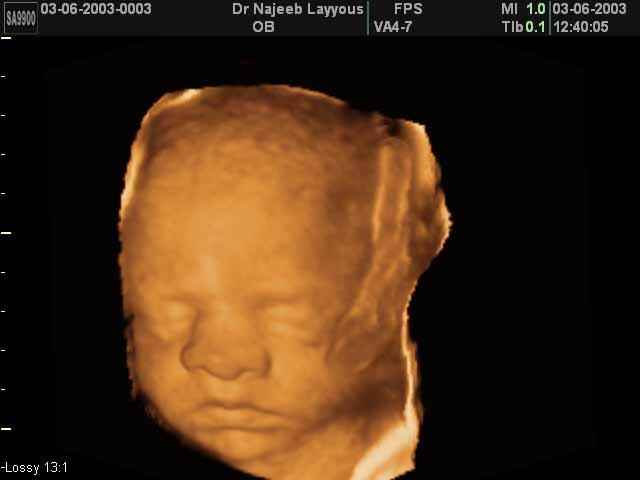

3D Fetal Face Ultrasound Scan Photos